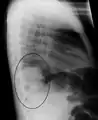

Right upper lobe pneumonia as marked by the circle.

Right lower lobe pneumonia as seen on a lateral CXR